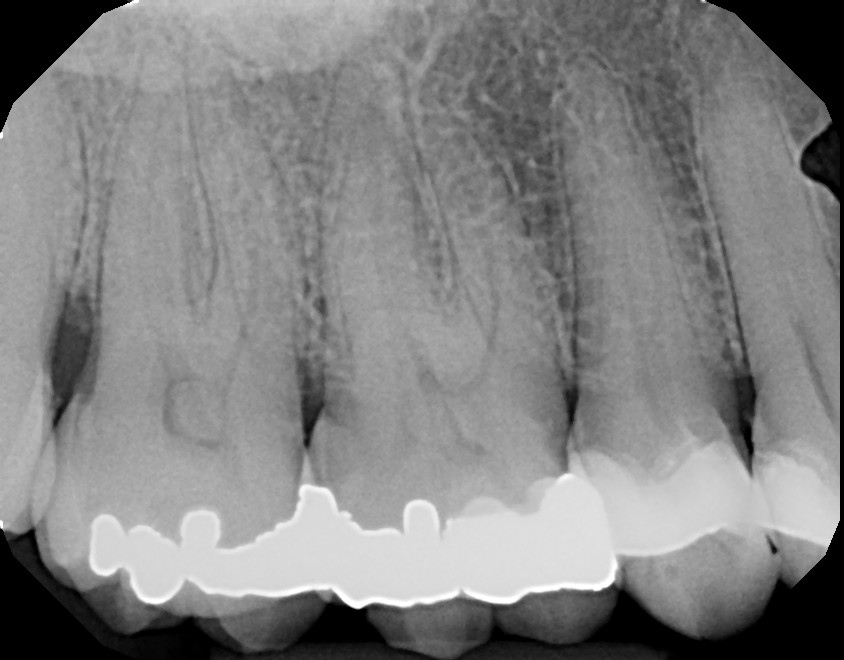

This is a first maxillary molar (tooth #3) that over time required a crown due to a large failing filling. On average, fillings last 5-8 years depending on the size and type of filling with proper oral hygiene, including daily flossing. This patient was advised of possible sensitivity that can occur after crown preparation. Prior to final/permanent crown cementation, tooth #3 became extremely sensitive to hot, cold, and bite and required root canal therapy. With patient education and referral to an endodontist, the final crown was not cemented on prior to root canal therapy. This avoided additional, unnecessary steps. Always ask your dentist/endodontist questions if you feel something doesn't feel right with your teeth, especially after dental work.